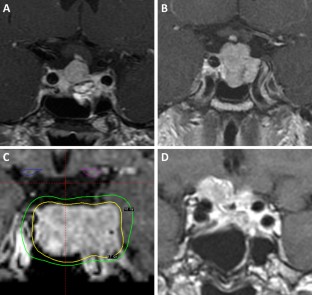

Five patients (four male, one female) having single-fraction SRS for persistent or recurrent SCO between 2002 and 2018. Median age was 56 (range 54–79) years. Pre-SRS treatments included transsphenoidal resection (TSR) (n = 3), multiple TSR (n = 1), and TSR, radiotherapy, and craniotomy (n = 1). Median target volume was 4.7 (range 1.8–8.4) cm3, with a median tumor margin dose of 17 (range 14–20) Gy. Median follow-up was 24 (range 10–69) months. All radiation-naïve patients achieved tumor control after SRS; tumor progression was noted 24 months after SRS in one patient who failed prior radiotherapy. No radiation-induced complications were observed after SRS. Systematic literature review of 43 cases in addition to the five cases presented here showed that tumor progression/recurrence was more frequent after STR compared to GTR (P < 0.001). Ten previous cases of radiotherapy for SCO have been reported, but most did not detail radiation volumes, doses, or outcomes.